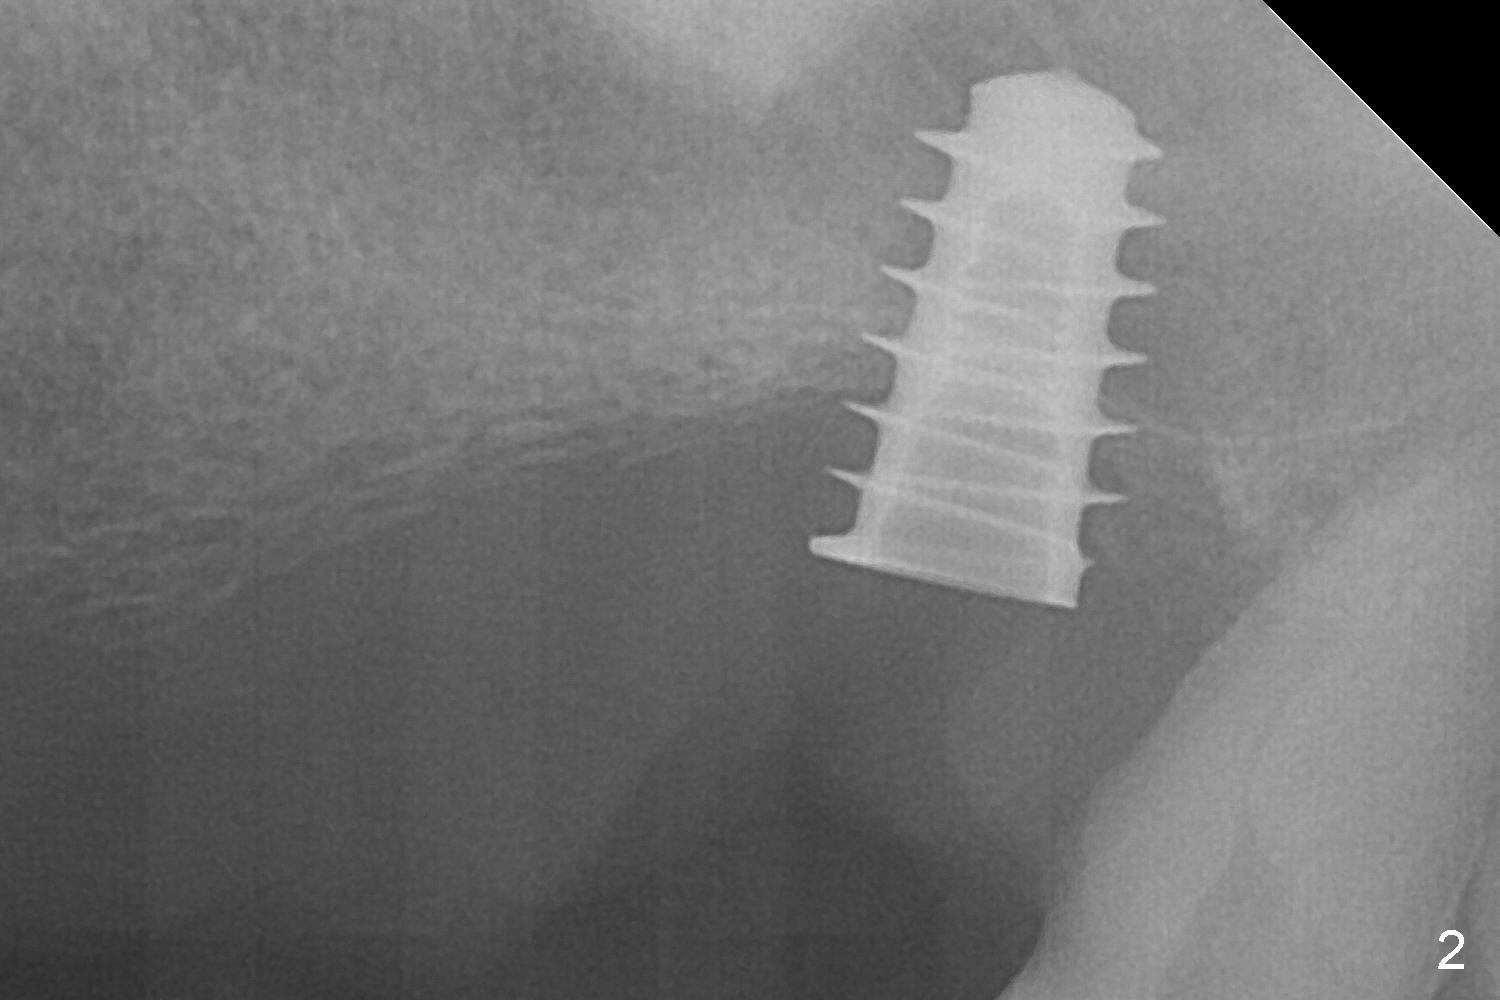

The posterior abutment of the 5-unit FPD, #15 is loose with the buccal roots extruded outside the sockets. The palatal socket is the appropriate site of immediate implant with the presence of the buccomesio-palatal walls, although short. The thinnest portion of the palatal socket is 1.6 mm (Fig.6 CBCT coronal section through the palatal root (P)). Magic Sinus Lifter cannot break through the sinus floor. UF drills are used to create osteotomy and sinus lift until 4.3 mm. A 5 mm tap drill is inserted without stability (Fig.1). A 5.5x9 mm IBS dummy implant achieves insertion torque of 10 Ncm, although it looks smaller (Fig.2) than the tap in Fig.1. After placement of PRF membrane and bone graft (allograft, autogenous bone and Osteogen, Fig.3 *), a 6x9 mm IBS implant is placed with insertion torque of 30 Ncm. It appears that the fins of the implant slice into the bone at high magnification for engagement. Following further placement of the implant, bone graft is packed into the distal portion of the socket (Fig.4 <). The thin fins extends into mesial and distal thicker bone (Fig.5 (CBCT sagittal view) *).